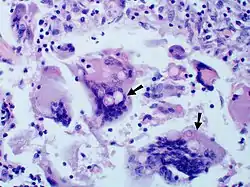

Large yeast-like fungi seen within giant cells at arrows.

Large yeast-like fungi seen within giant cells at arrows.Budding yeasts in cytoplasm of giant cells at arrows. Broad-based budding and double contoured cell wall seen in the giant cell in the center is characteristic of Blastomyces dermatitidis.